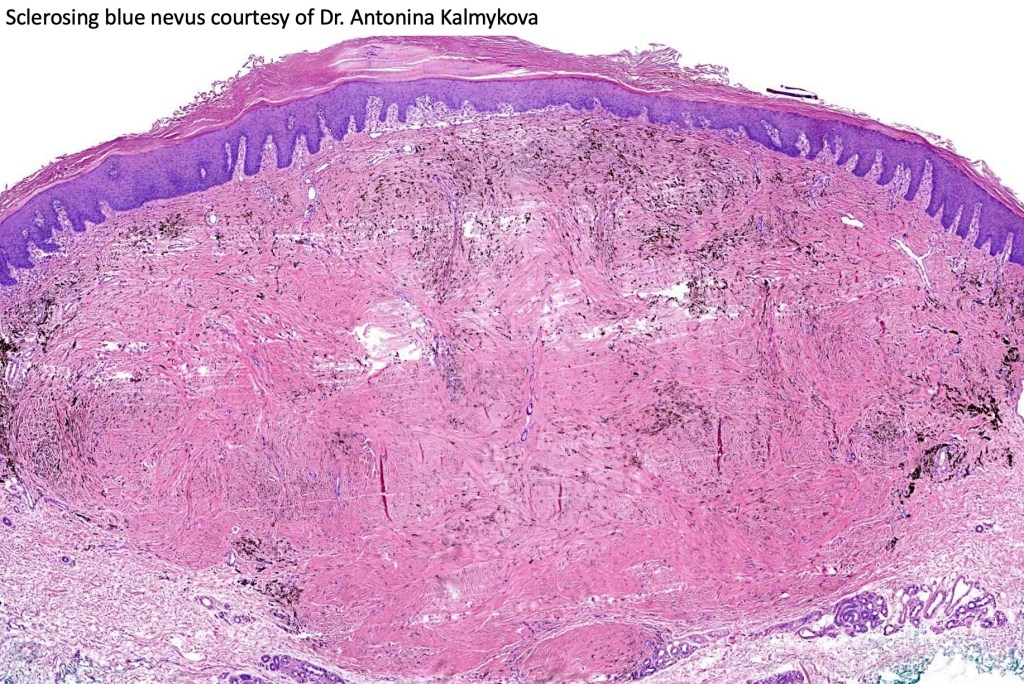

•Most characteristic is the dumbbell silhouette although a plague morphology may also be encountered

•Stromal fibrosis, myxoid change, vascular hyalinization with cyst formation are often seen

•Desmoplastic variant